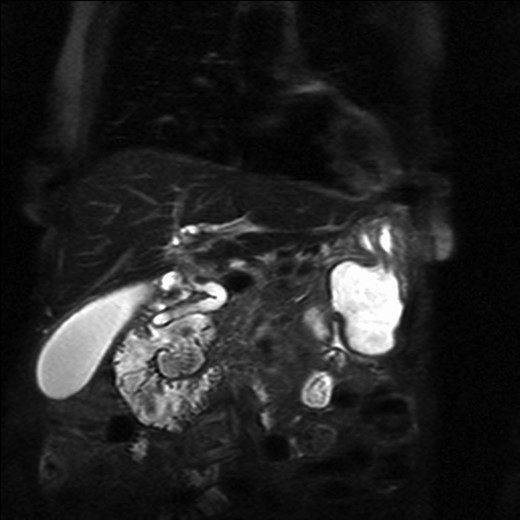

The patient underwent an MRCP which demonstrated mild distension of the gallbladder with several calculi. There was intra- and extra-hepatic biliary dilatation to the level of the ampulla. A very large fluid and air filled periampullary duodenal diverticulum measuring ~8 cm in the long axis was also noted (Figs 1–3). This finding was unchanged compared to a CT study from 6 months previously. The CBD was dilated to the level of this diverticulum and the cause of the patient’s biliary dilatation and obstruction. Interestingly, an unusual appearance to the kidneys was recorded with multiple microcystic changes in both kidneys, which is typically reported in patients with lithium induced renal disease. A gastroduodenoscopy revealed a large periduodenal diverticulum in D2 (Fig. 4).

Magnetic resonance imaging with a giant duodenal diverticulum.